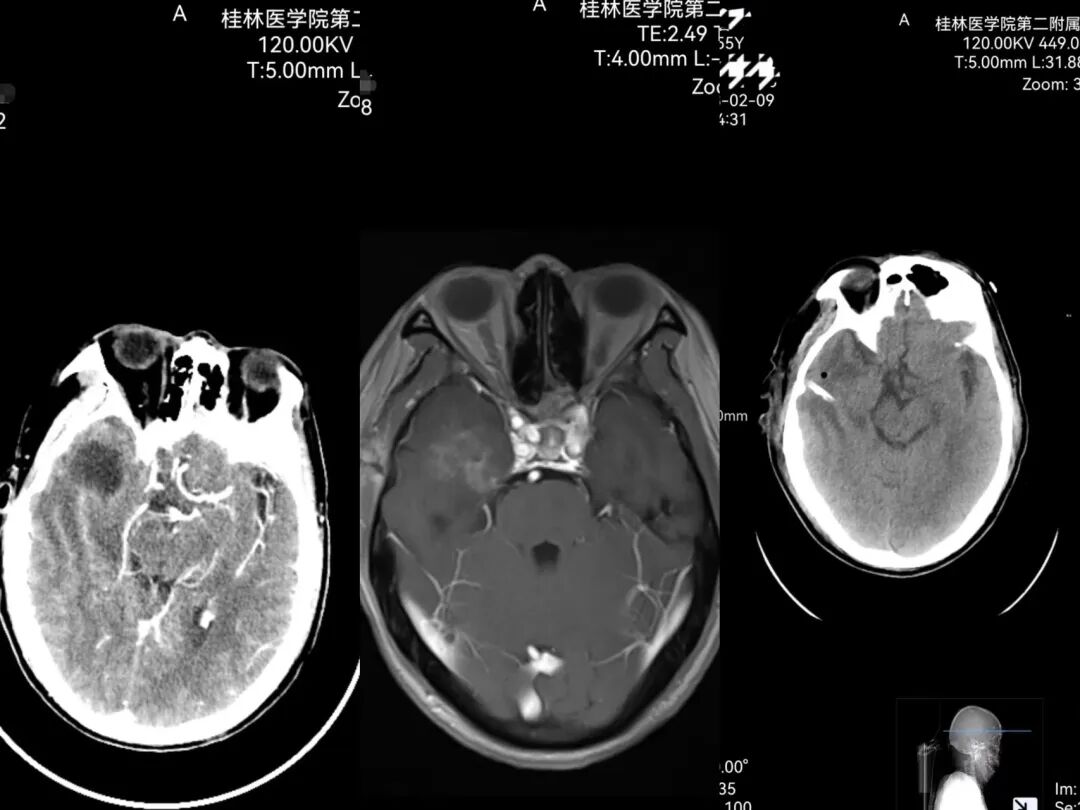

患者李先生,55岁,突发头痛、左侧肢体无力40小时入住神经外科,经查后确诊为颅内感染,并伴有右侧颞叶脑脓肿。在所有的感染性疾病当中,颅内感染是最严重的一种,也是中枢神经系统较为严重的疾病之一。

针对患者的情况,科室负责人李深誉团队考虑该疾病常规抗感染治疗无明显好转,经过讨论分析,为减少对病人颅内重要功能区的手术创伤,提高病人的预后,决定对患者实施脑室外穿刺引流+腰大池置管引流+脑脓肿穿刺引流术。

术后病人成功复苏,言语清晰,左侧肢体肌力较术前明显好转,术后复查CT提示颅内脓肿完全消失。术后经过神经外科医护团队的精心治疗,病人体征逐步恢复正常,同时神志恢复清醒,手术取得了满意的效果,日前患者已顺利出院。